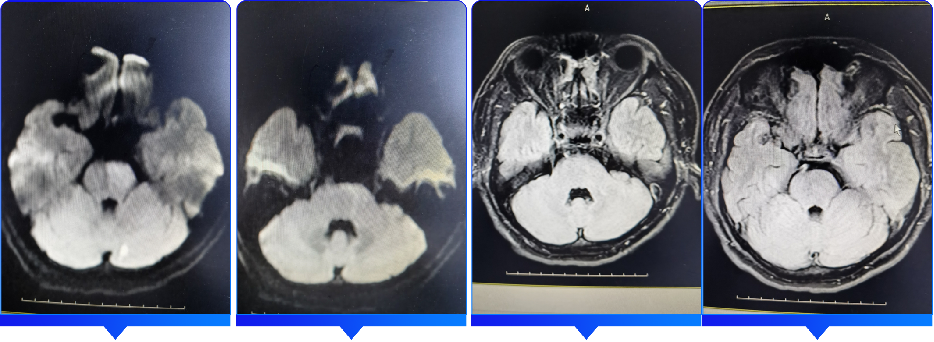

术前影像学检查结果

颅脑CT(2021.12.04)提示:未见明显异常。

颅脑MRI+MRA(2021.12.04)提示:左侧小脑、脑干急性期脑梗死;基底动脉闭塞。